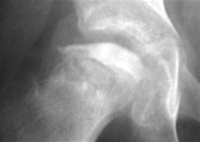

- Mb Calvé-Legg-Perthes er en atraumatisk opstået avaskulær nekrose i hoftehovedets epifyse

- Typisk ses hoftesmerter hos et barn mellem 4 og 10 år uden anden oplagt årsag til hoftesmerter